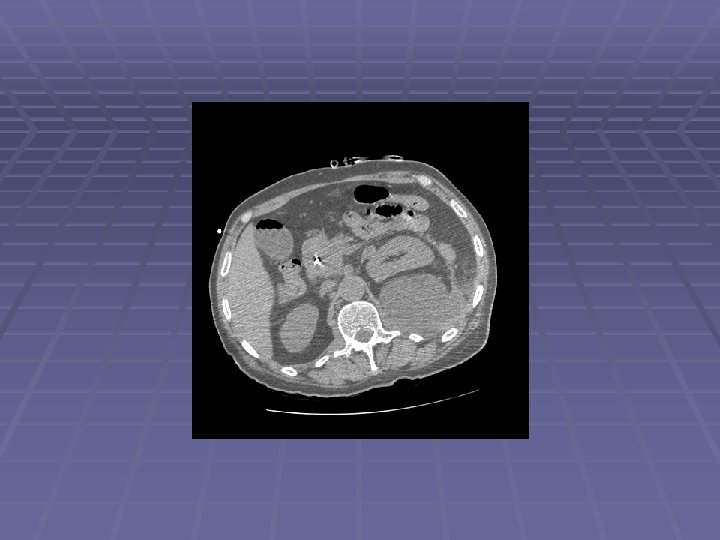

Patient DD 62 y. o. man with history of alcoholism and recurrent pancreatitis since the 1970’s, admitted to an outside hospital with jaundice MRI showed a large pancreatic head mass ERCP for biliary drainage – failed Complicated PTC by pancreatic tail pseudocyst formation with internalization - successful Patient left AMA and came to JMC EUS/FNA performed to obtain diagnosis

Endosonographic Evaluation EUS Large ~30 mm hypoechoic pancreatic head mass surrounding the intrapancreatic CBD with PTC drain seen within CBD Dilated PD to 5 mm with evidence of chronic pancreatitis FNA performed